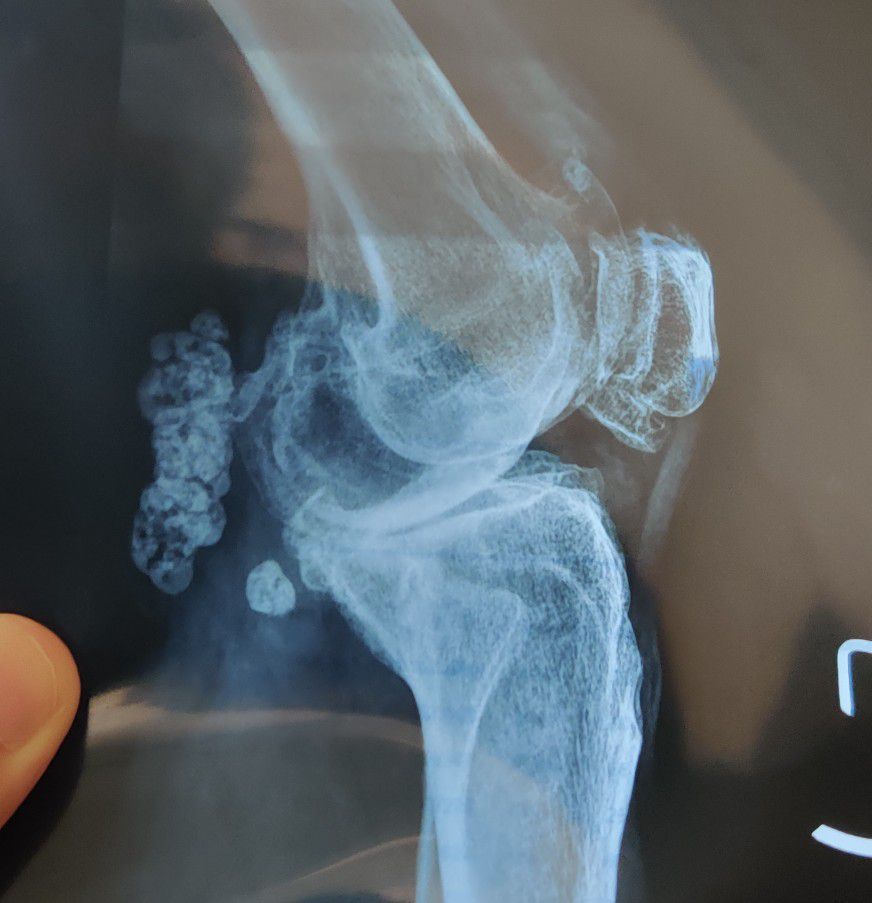

What is the Diagnosis?

Xray

Orthopaedics

Kneejoint